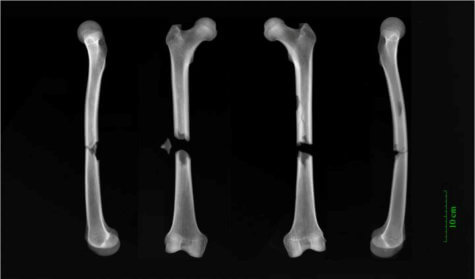

In fact, the most extreme injuries belonged to that friar. Identified by his burial place and belt buckle, the man suffered two broken thigh bones in the accident which likely ended his life.

“The friar had complete fractures halfway up both his femurs,” adds Dr. Dittmar, from the After the Plague project at Cambridge’s Department of Archaeology. “The femur [thigh bone] is the largest bone in the body. Whatever caused both bones to break in this way must have been traumatic, and was possibly the cause of death. Our best guess is a cart accident. Perhaps a horse got spooked and he was struck by the wagon.”